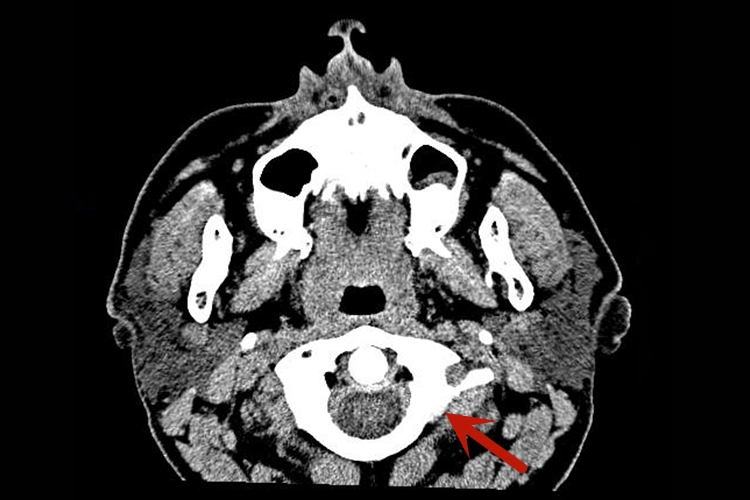

腮腺:CT图像上,腮腺位于下颌骨后,胸锁乳突肌前,上至颅底,位于乳突尖和颞颌关节之间,下至下颌角。腮腺是脂肪性腺体组织,密度低于周围的肌肉密度,但高于皮下、颞下窝及咽旁间隙内的脂肪。在腮腺实质内的血管能清楚显示,在增强图像显示更清楚。腮腺导管造影后CT扫描,能清楚勾画出导管的解剖结构,显示其粗细、走行及其变异。

颌面部CT对于颌面部组织病变的发现、诊断及其范围确定等,均有重要价值。比如通过CT下腮腺腺体形态、大小和密度的变化,可以判断病变的部位及蔓延范围,良性肿瘤与恶性肿瘤的鉴别,以及腮腺外肿瘤的侵犯。

若有良性肿瘤,其CT特征是肿块多呈类圆形,边缘光整,密度均匀,其中血管瘤有明显强化。恶性肿瘤的形态多不规则,边界模糊,密度不均匀,肿块内常有出血、坏死或囊变,常侵犯周围软组织及脂肪间隙,颅底骨质破坏及淋巴结转移。